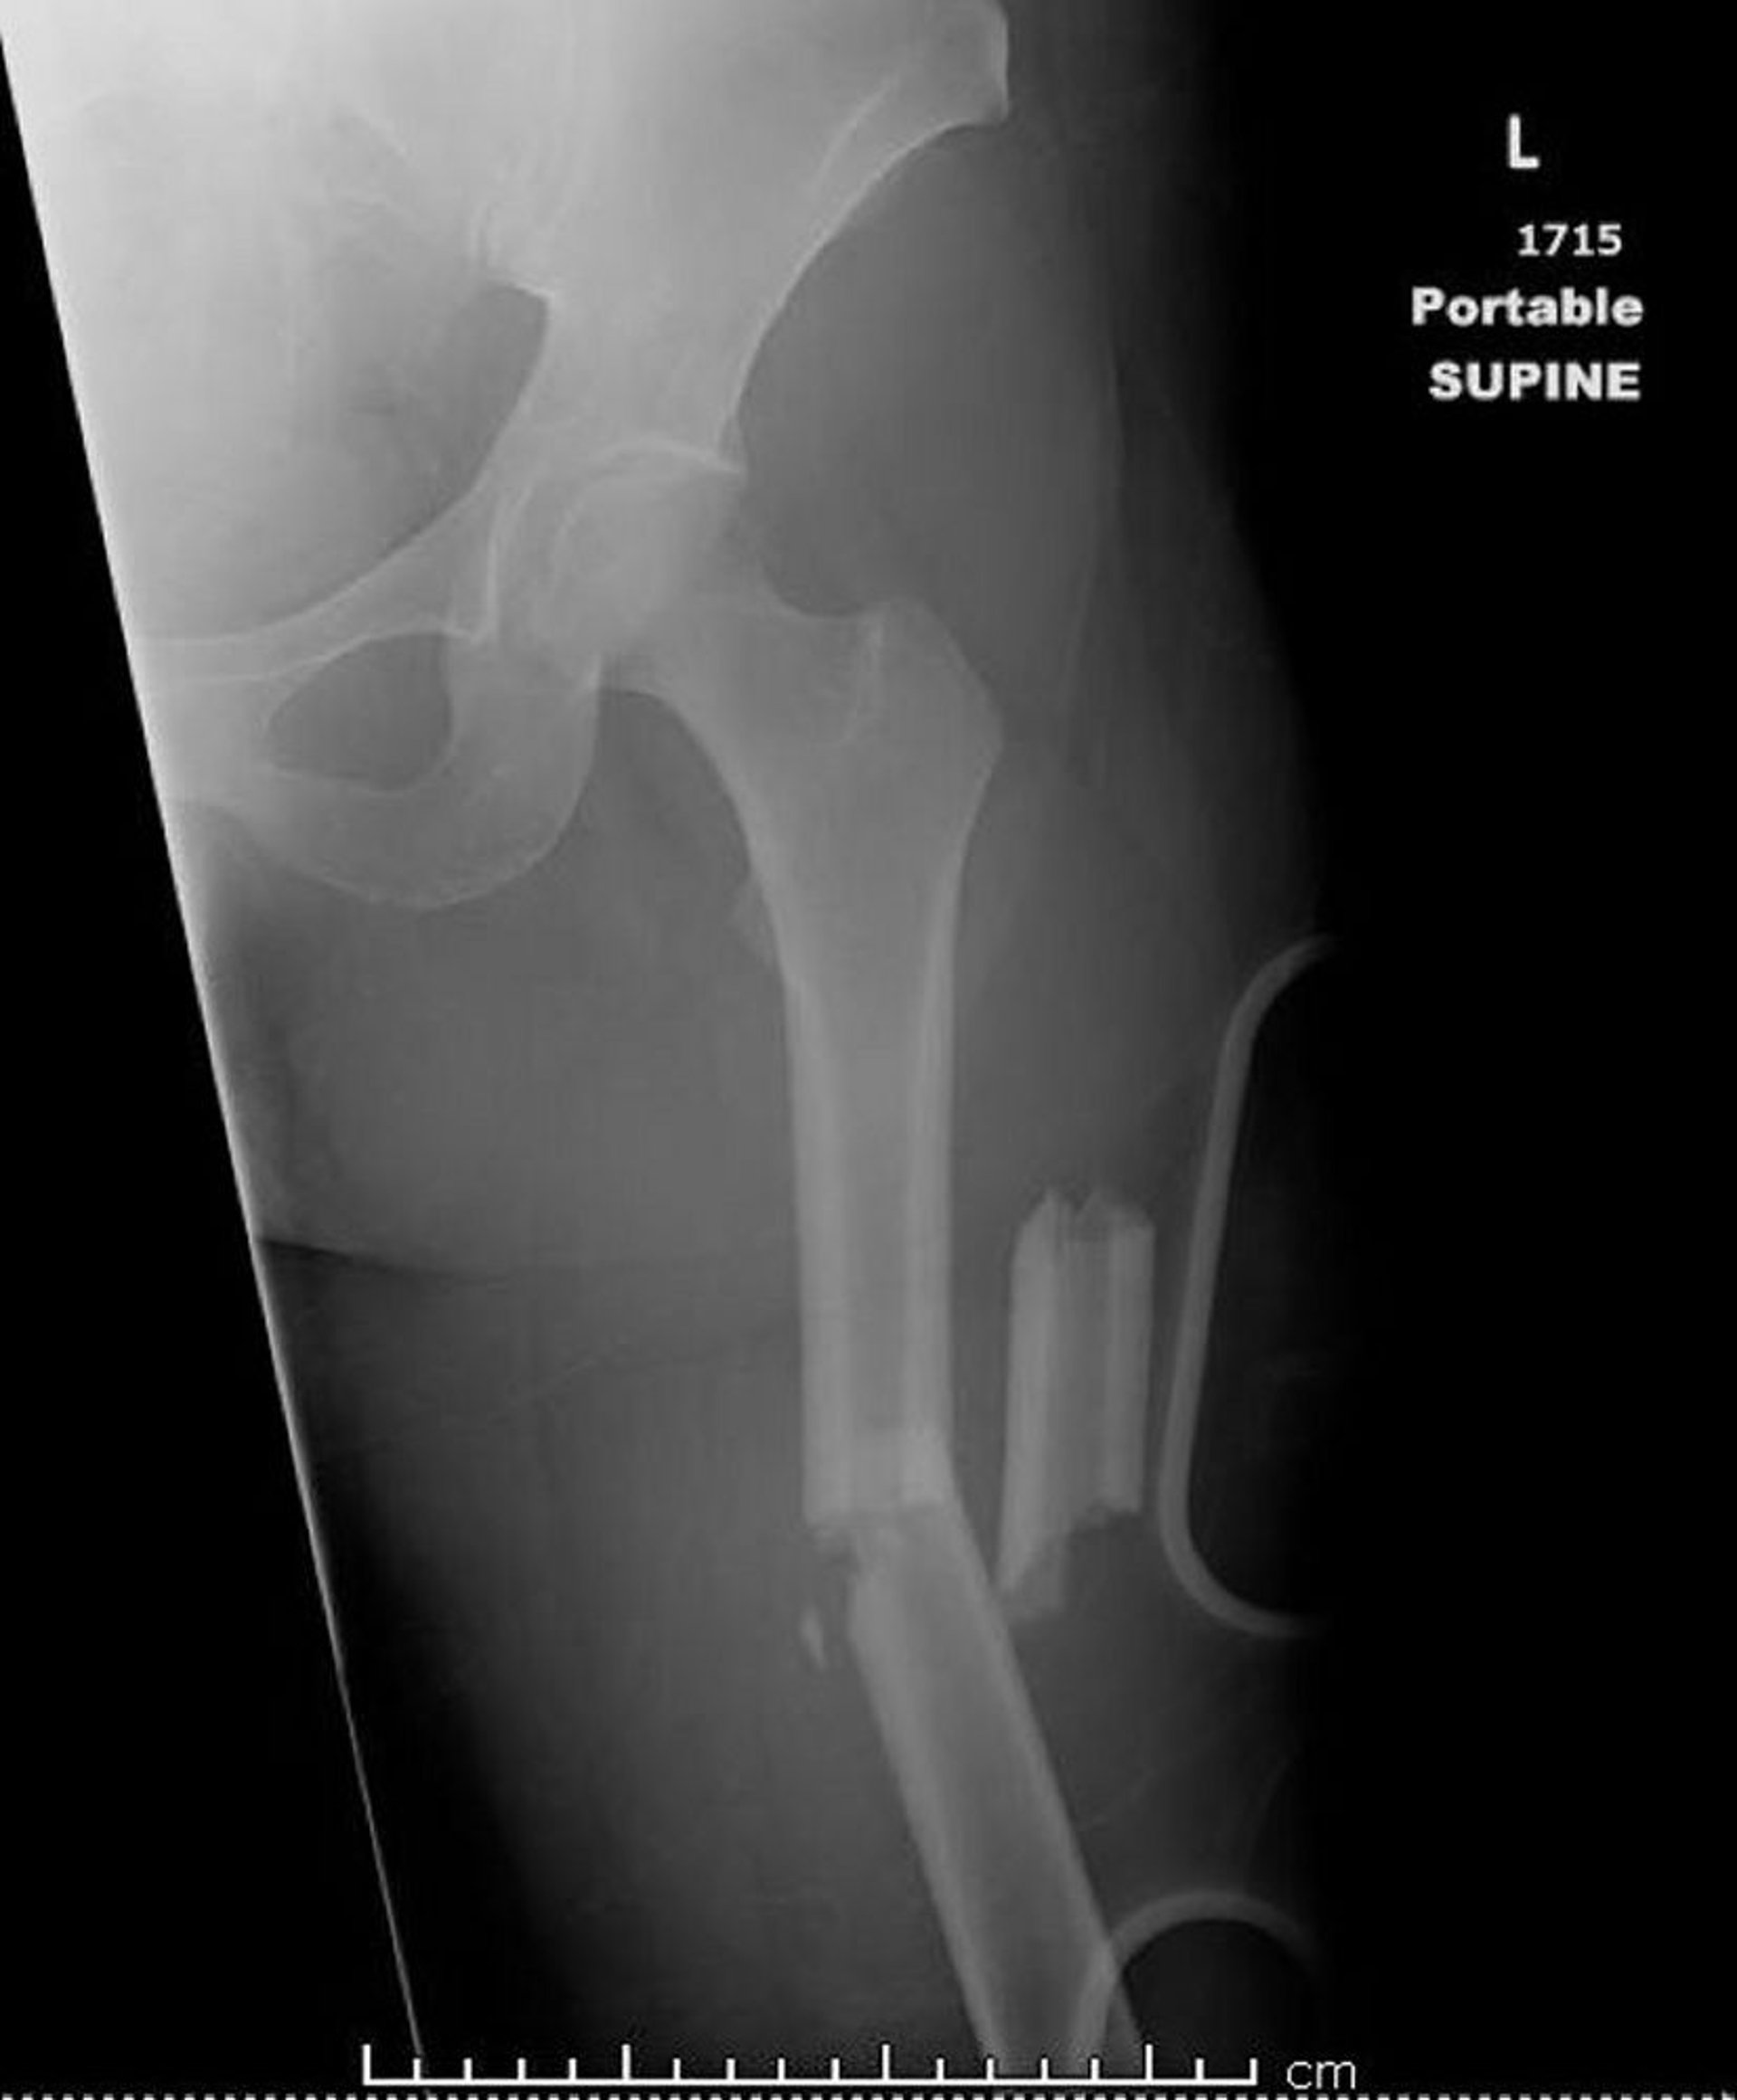

Frattura diafisiaria del femore

L’immagine mostra un femore fratturato in più di due punti (frattura comminuta).

Immagine per gentile concessione della dottoressa Danielle Campagne.